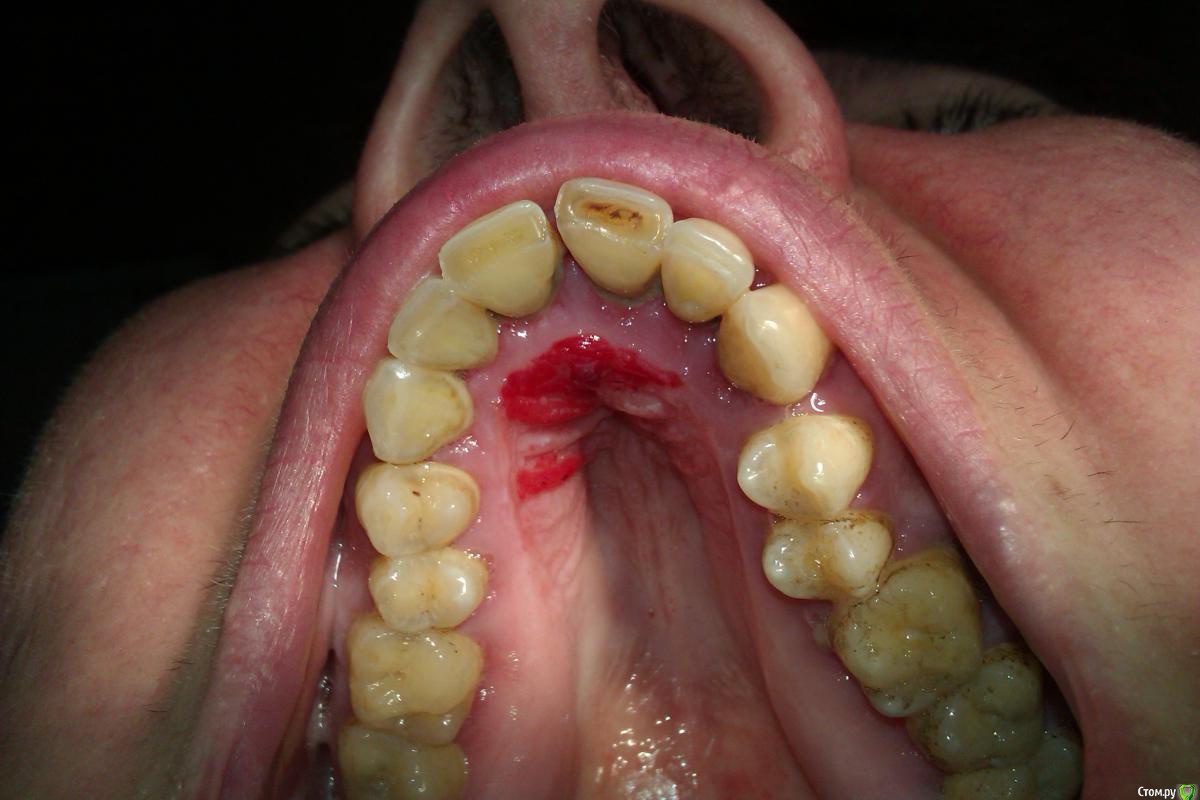

Iwan Опубликовано 25 октября, 2015 Поделиться Опубликовано 25 октября, 2015 Пациентке 50 лет. Никогда не обращала внимание на это образование. При пальпации оно мягкое безболезненное. Со слов женщины травмы не было.Придет в понедельник посмотрю в динамике. Что это может быть? Думаю отправить к онкологу на консультацию Ссылка на комментарий

gum Опубликовано 25 октября, 2015 Поделиться Опубликовано 25 октября, 2015 Мб это геморрагический васкулит или др проблема с сосудами, тк по фото на лице просвечивают сосуды и много, пососала конфету или просто создала в полости рта чрезмерное давление и в итоге "поломались" сосуды следовательно кровоизлияния. Как вариант? 1 Ссылка на комментарий

Iwan Опубликовано 25 октября, 2015 Автор Поделиться Опубликовано 25 октября, 2015 Как вариант принимается. Завтра она ко мне придет и проверим этот вариант. Если это простое провоизлияние картина должна будет измениться, все таки прошло 4 дня. Ссылка на комментарий

Iwan Опубликовано 26 октября, 2015 Автор Поделиться Опубликовано 26 октября, 2015 Мб это геморрагический васкулит или др проблема с сосудами, тк по фото на лице просвечивают сосуды и много, пососала конфету или просто создала в полости рта чрезмерное давление и в итоге "поломались" сосуды следовательно кровоизлияния. Как вариант?Спасибо, Вы оказались правы! Сегодня она пришла, слизистая как у младенца) как будто ничего и не было. Посоветовал обратиться к гематологу Ссылка на комментарий